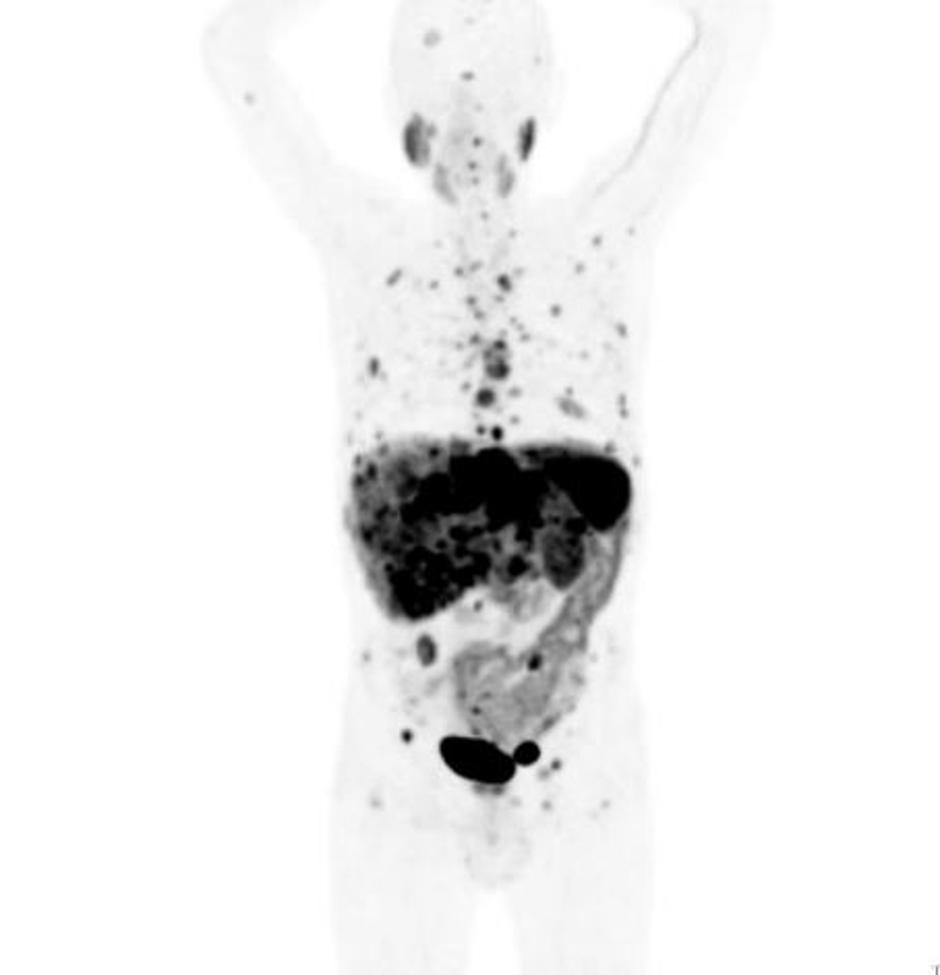

Na kliniki za nuklearno medicino Univerzitetnega kliničnega centra (UKC) Ljubljana so v teh dneh predstavili nov diagnostični pristop ugotavljanja prisotnosti in razširjenosti nevroendokrinih tumorjev ter spremljanju učinkovitosti zdravljenja teh bolnikov.

Nevroendokrini tumorji je krovno ime za skupino počasi rastočih rakov, ki se razvijejo iz celic endokrinega sistema. So redki, a se je število bolnikov v treh desetletjih podvojilo. Diagnosticiranje nevroendokrinih tumorjev je težavno zaradi počasne rasti, neznačilnih simptomov v začetku bolezni in različnih znakov in simptomov.

V UKC Ljubljana je tako na voljo najboljša metoda diagnostike nevroendokrinih tumorjev doslej. S pomočjo PET/CT preiskave, pri kateri uporabijo galij-68, se lahko pravočasno postavi diagnozo, oceni stanje bolezni in izbere najboljše zdravljenje oziroma zazna spremembo bolezni. "Navadno odkrijemo od 65 do 70 odstotkov nevroendokrinih tumorjev, z novo metodo z galijem-68 pa jih

odkrijemo 90 odstotkov ali več. Gledano globalno je to najbolj učinkovita diagnostika,"

je povedal doc.dr. Luka Ležaič iz Klinike za nuklearno medicino.

Preiskava pomembno dopolnjuje nuklearno-medicinsko metodo zdravljenja nevroendokrinih tumorjev – ciljano molekularno radionuklidno terapijo, ki je v UKC Ljubljana že v uporabi.

Odkrivanje nevroendokrinega tumorja (NET), redke vrste raka, za katero je umrl nekdanji predsednik uprave podjetja Apple Steve Jobs in ki se pogosto zamenjuje z bolj agresivnim rakom trebušne slinavke, je težko in zapleteno. Bolezen namreč poteka z neznačilnimi simptomi, včasih jih sploh ni, pojavijo pa se tudi takšni simptomi, ki lahko kažejo na druge bolezni.

V Sloveniji vsako leto odkrijejo od 80 do 100 novih bolnikov s temi običajno zelo počasi rastočimi raki. Najpogosteje jih najdejo v pljučih in prebavnem sistemu, čeprav lahko izvirajo tudi iz drugih delov organizma, na primer iz trebušne slinavke, mod ali jajčnikov. Lahko se razširijo in metastaze pogosto najdejo tudi v jetrih ali limfnih vozlih. Zdravje Za abrahama so mu prijatelji podarili ultrazvočni pregled in mu rešili življenje